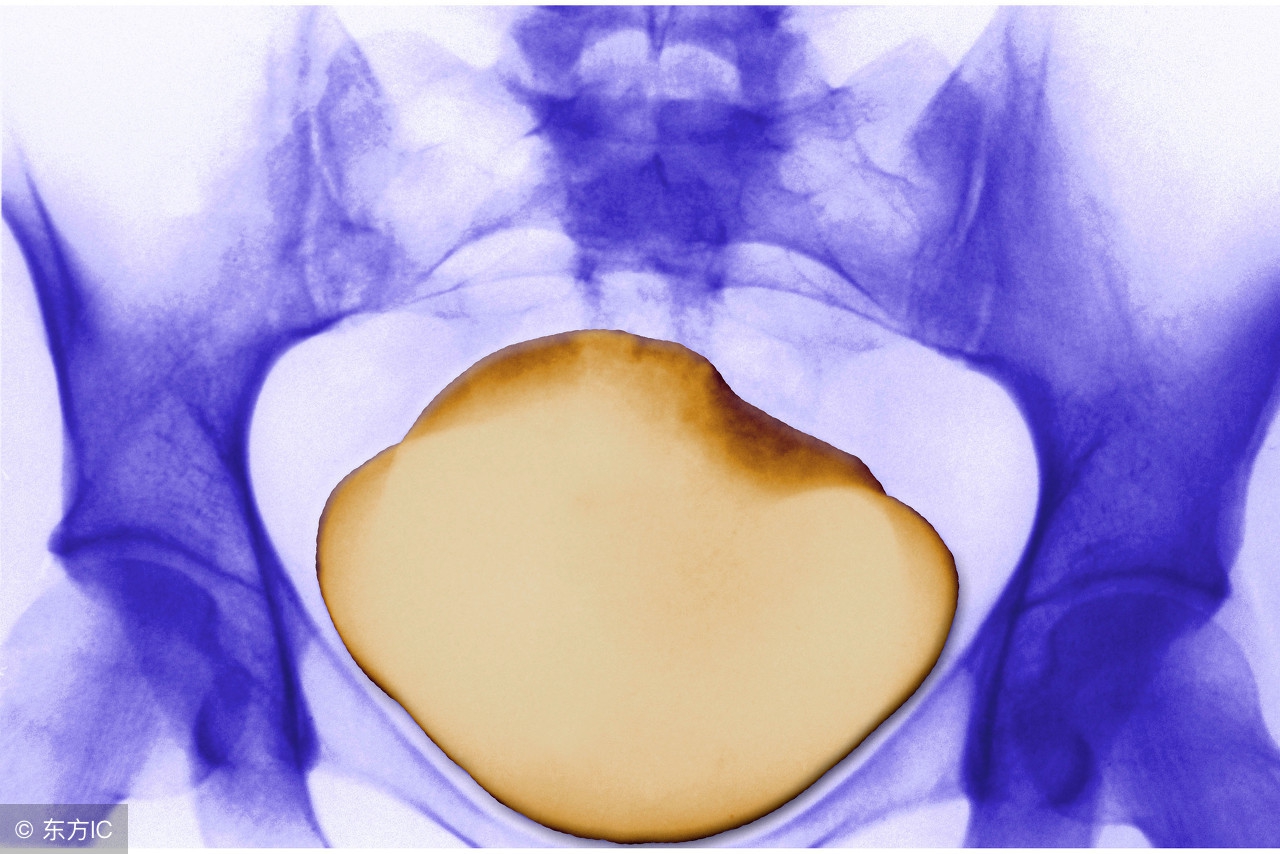

肾盂肾盏不会蠕动,若是这些部位有结石,即使石头比较大,却也不会引起绞痛,常常是在体检中才被发现。即使出现较严重的肾积水,也只是引起同侧腰部较为轻微的胀痛。

无痛大结石也要取

较大的肾结石,即使不痛,也要积极处理,否则形成梗阻、肾积水,损伤肾功能。此时采用中药治疗疗效不太好。长径2cm以下的肾结石可优先考虑分次做体外冲击波碎石,配合中药排石。较大的结石则应选用腔镜微创或开放手术。